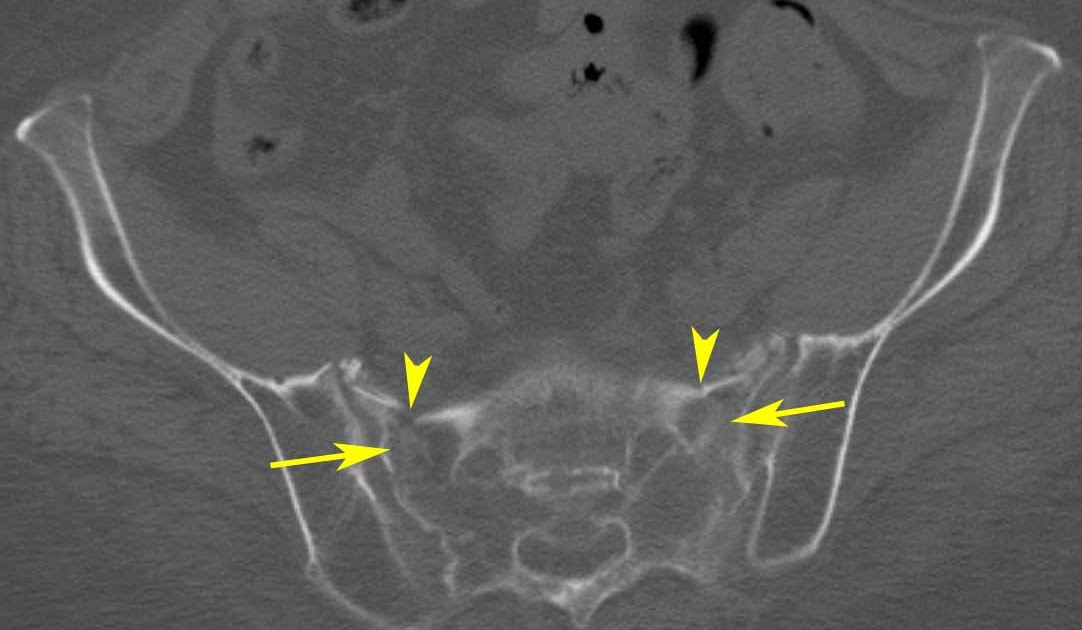

When the sacrum is fractured, 60 percent of the time the bone in front. In this context, sacral insufficiency fractures (sifs) may be an important causative factor for increasing morbidity of patients. Sacral insufficiency fractures (sifs) are easily neglected by clinical physicians. Pelvic insufficiency fracture (pif) associated with radiation therapy for gynecologic cancers is high (14%); Most patients have delay in the diagnosis of sacral fracture as the symptoms can be more vague. Insufficiency fractures of the sacrum are an underrecognized cause of low back pain, particularly in the elderly female. Coronal inversion recovery mri shows an area of hyperintensity in the right sacral ala (white. Fracture delayed healing caused by ineffective immobilization due spontanee du sacrum par 'insuffisance'. The fracture can just simply happen when the bone becomes too weak to handle the stress of weight bearing. Neurosurgery, radiology, pain management keywords: An unsuspected cause of low back pain in elderly women. Sacral insufficiency fracture is an underdiagnosed debilitating condition that clinicians should be aware of in patients presenting with lower back pain. The combination of low bone density and increased activity blurs the boundary between fatigue and insufficiency fractures in many runners. Symptoms included lower back or buttock pain @article{schindler2007sacralif, title={sacral insufficiency fractures}, author={o. Sacral insufficiency fractures are relatively common but are often underdiagnosed and undertreated. Mri is the preferred radiologic technique because of. American journal of radiology 1985;